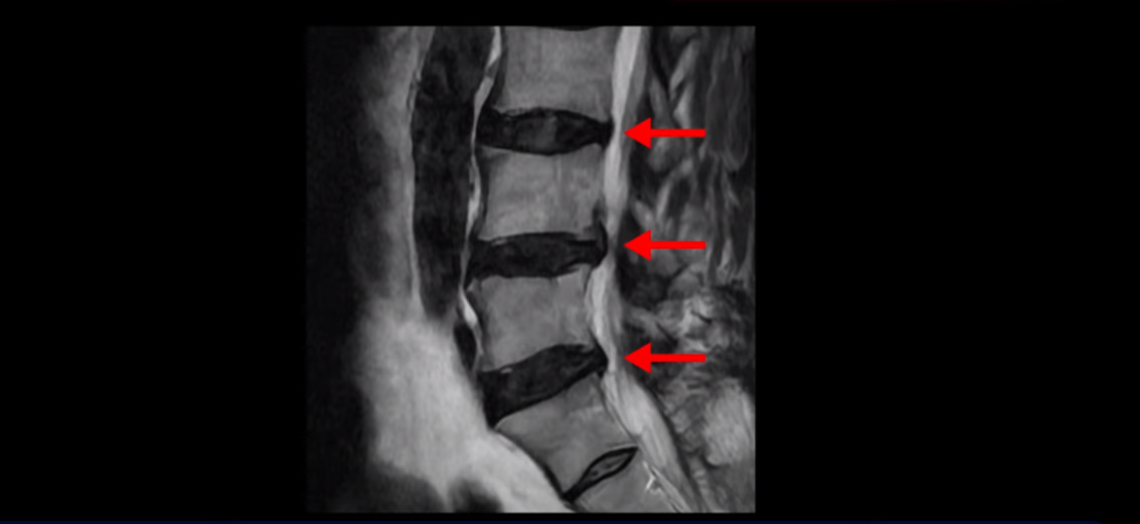

이분 MRI를 보면 허리 세 마디 정도의 퇴행성 디스크가 있고

4번 5번 마디에는 중심성 협착이 있습니다.

후관절과 황색인대가 두꺼워져 있어서 척추관이 좁아져 있습니다.

하지만 이분의 갑작스러운 통증을 일으키는 원인은 4번 5번에 발생한 디스크 파열입니다.

이분은 왼쪽 무릎 아래로 본인 표현으로는 다리를 잘라 버리고 싶다고 할 정도의 심한 통증이 있는데 보통 이런 표현은 디스크 파열이 발생했을 때 많이 사용하는 표현입니다. 이분 4번 5번 디스크를 자세히 보면 왼쪽으로 파열되어 밀려 올라간 디스크 수핵을 볼 수 있습니다.

옆에서도 보이지만 단면에서도 왼쪽으로 심하게 밀려나온 수핵이 잘 보입니다.